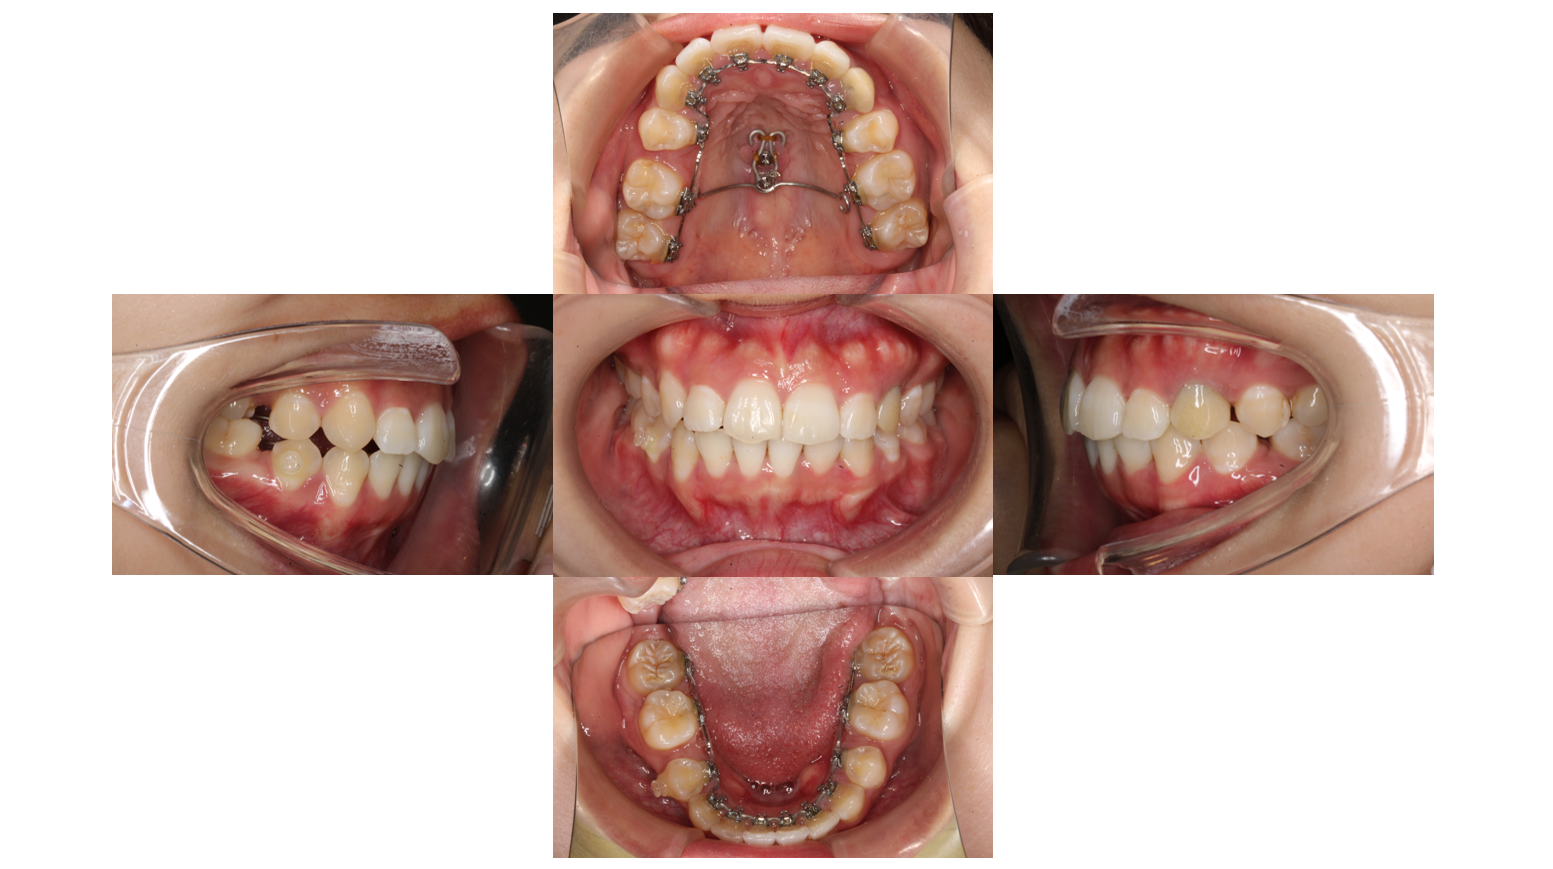

1年経過

前歯を後ろに下げるためにフックにゴムかけしていきます

1年11か月経過

全体的に隙間が空いてこないようにゴムかけをしていきます